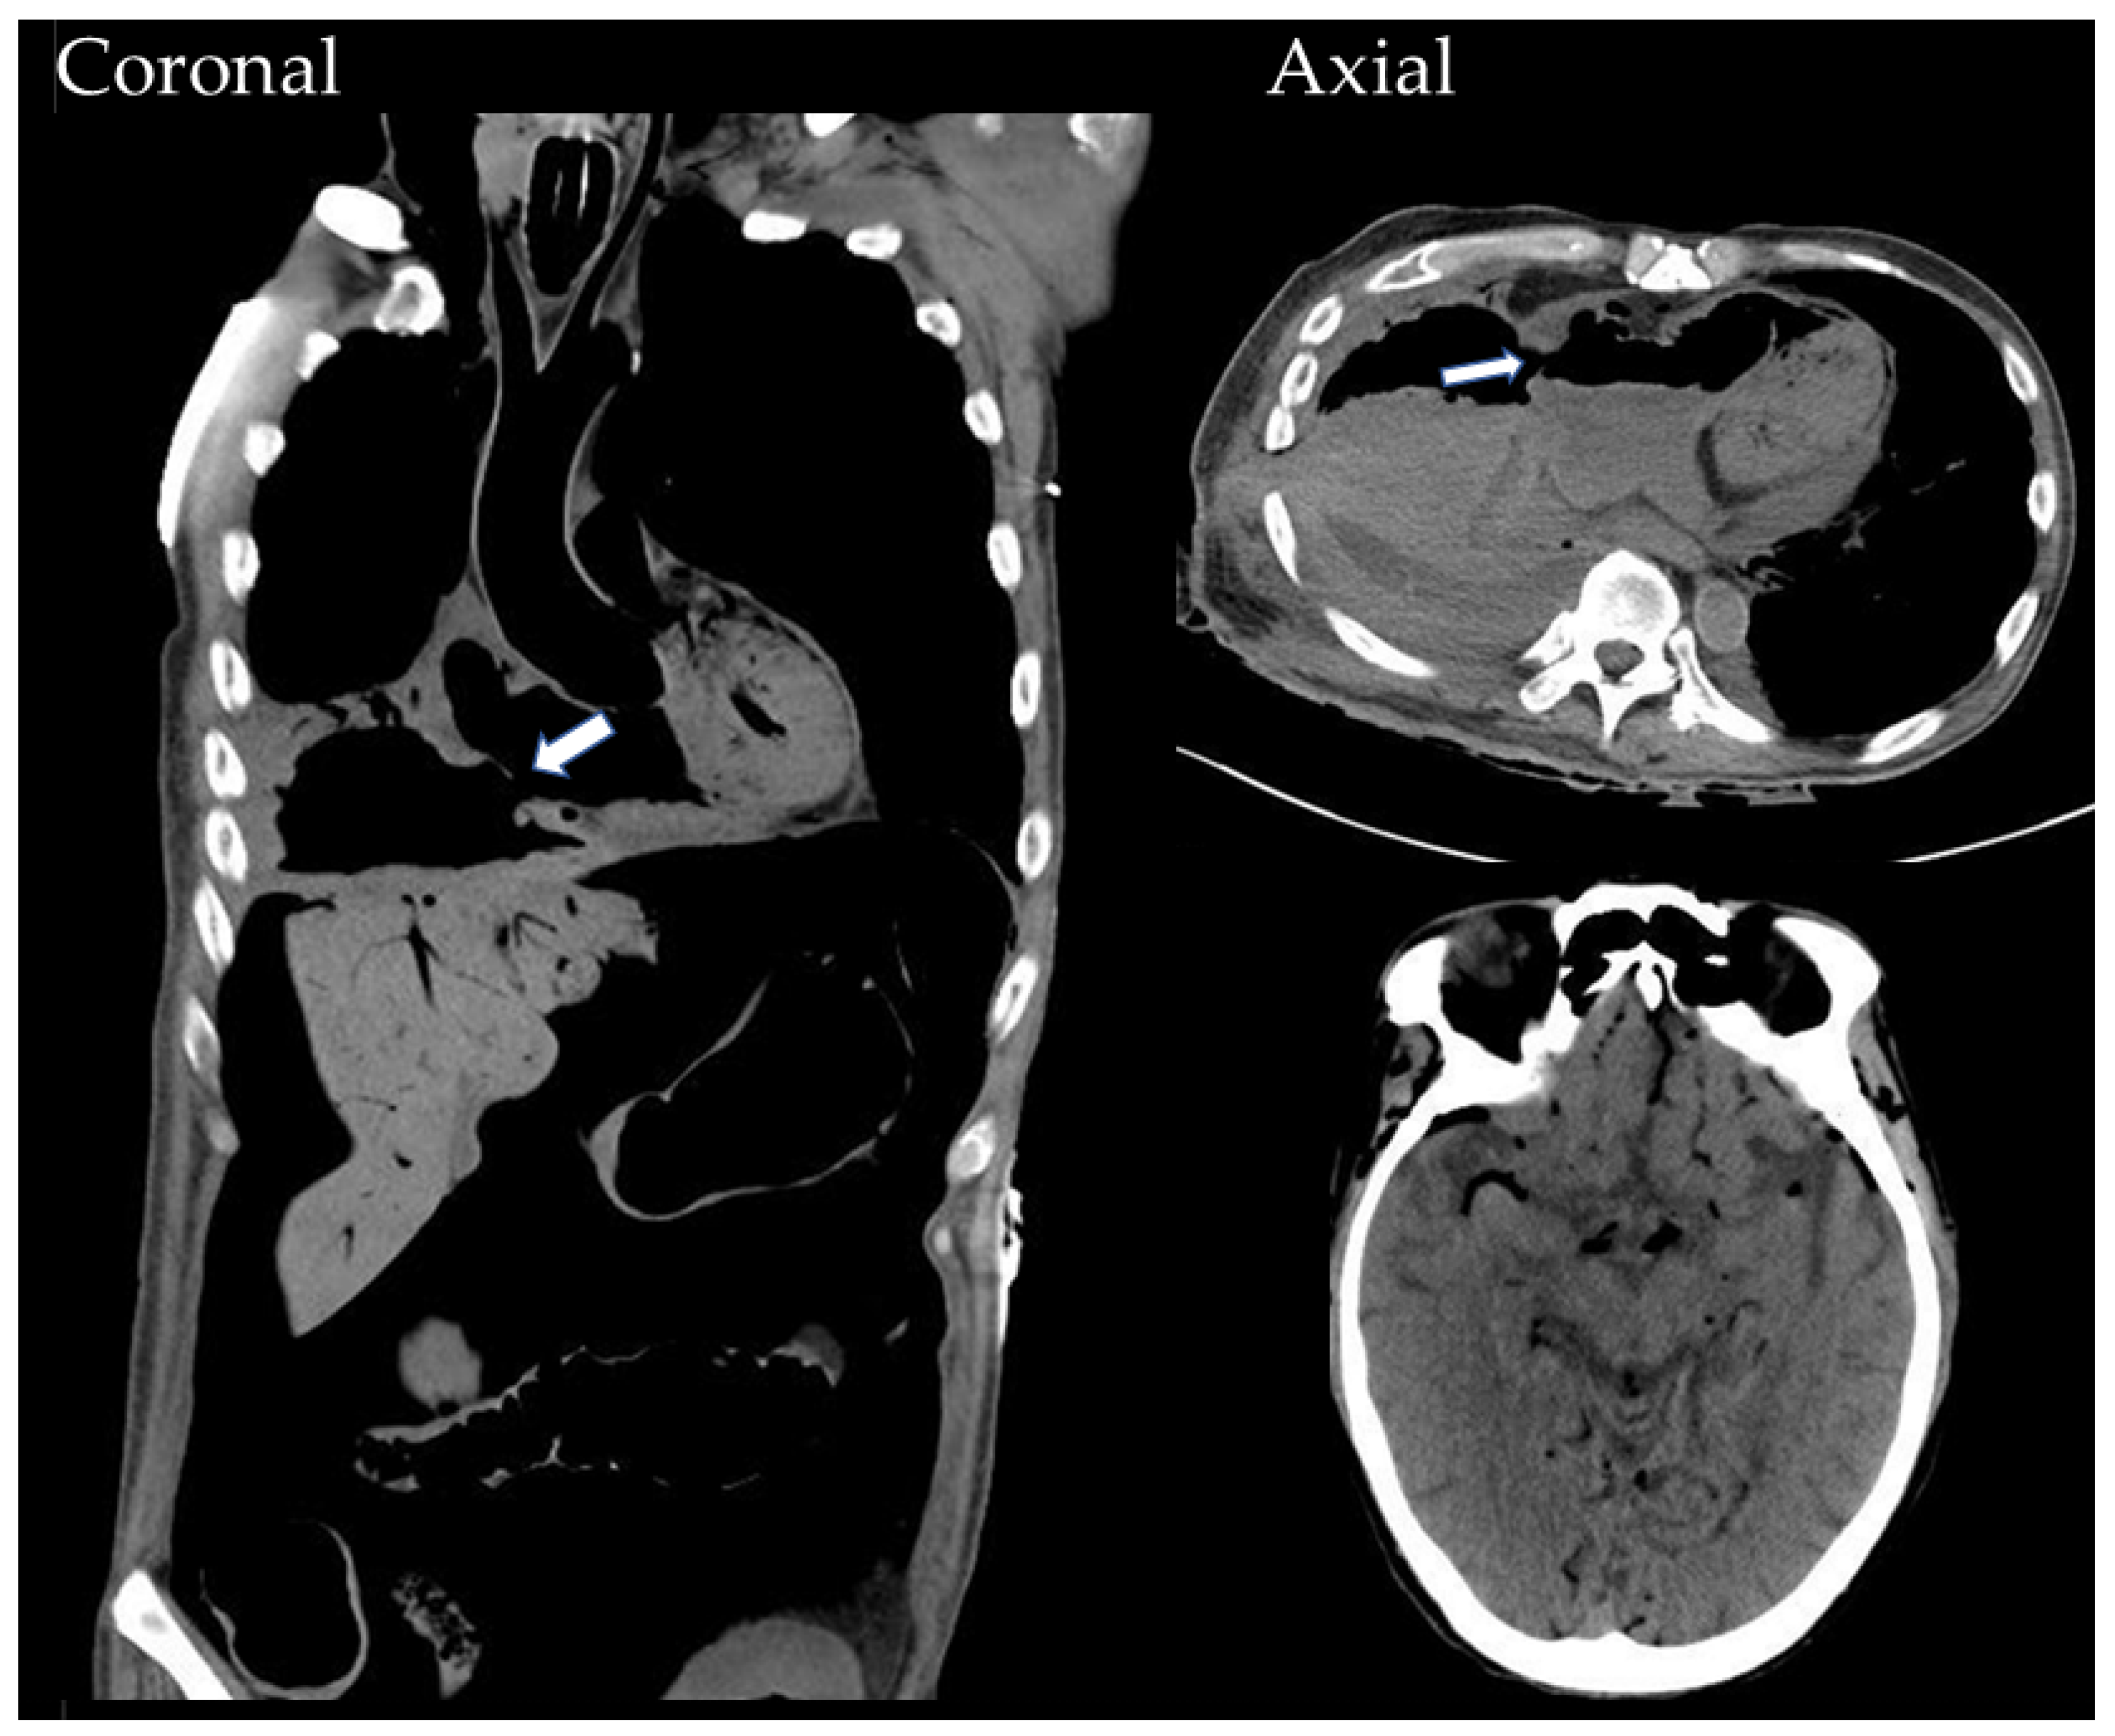

2. Case History